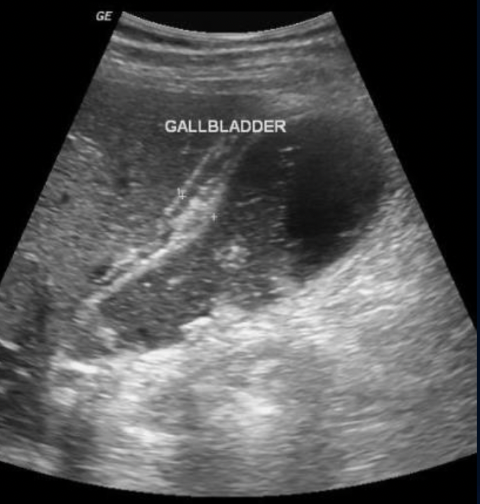

Path?

Cholelithiasis